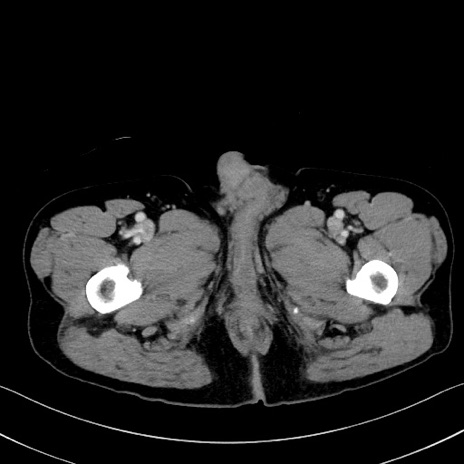

症例35(横断像)

【症例】70歳代 男性

【主訴】腹部膨満、嘔吐

【現病歴】昨日より腹部膨満感出現。本日増悪し、仙痛出現。嘔吐あり、受診。

【既往歴】糖尿病、胆摘後

【身体所見】BP 149/80mmHg、HR 74/min、BT 35.9℃、腹部:膨満、軟、圧痛なし。腸雑音減弱あり。上腹部正中切開瘢痕あり。

【データ】WBC 13500、CRP 1.72

冠状断像